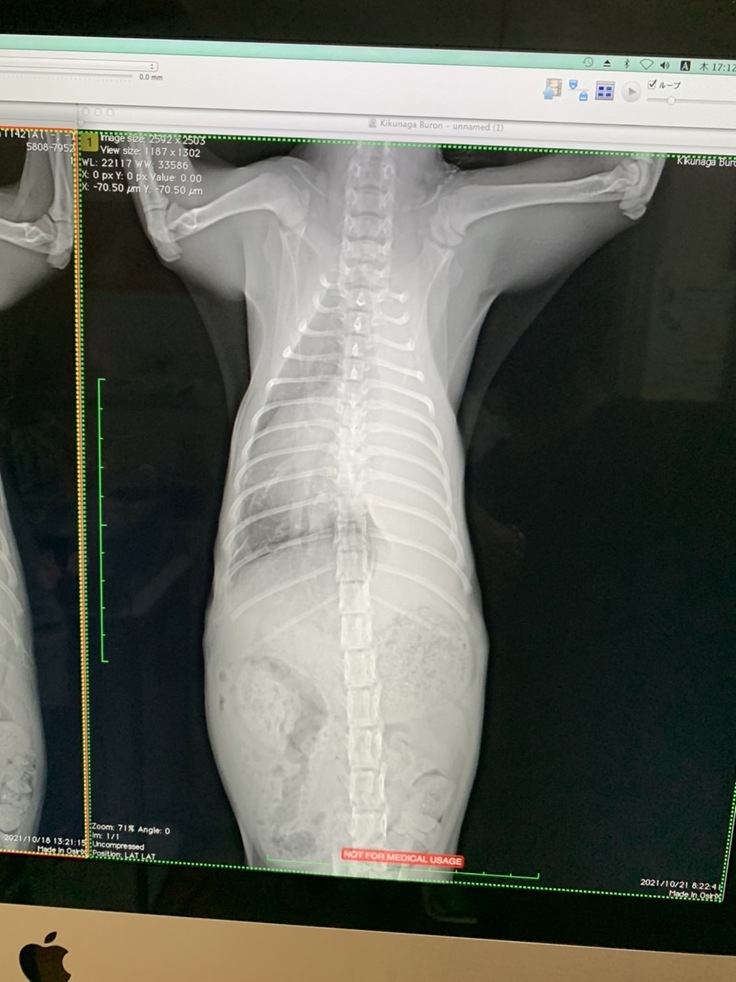

レントゲン検査の結果:胸水で圧迫され心臓が右側によっている。

レントゲン検査の結果、左肺が真っ白に写っていました。胸腔内に胸水が溜まっていて、胸水が肺を圧迫していたたため、白くなっているのは酸素が入っていないことを示し、左肺がしぼんで機能していない状態でした(無気肺)。心音もほとんど聞こえない状態でした。この状態が続くと肺が元通りにはふくらまない、もしくは急にふくらんだ場合、毒素が全身に回り危険な状態になるという説明を受けました。

肺のレントゲン

レントゲン検査

わずかですが、白い部分が減ってきています。

左肺の胸水も減ってきて、黒い部分がかなり広がってきました。